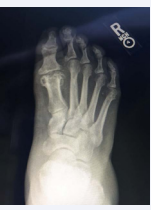

Before any treatments are offered a series of radiographs should be taken to assess the pathology of the first MPJ. This usually consists of the lateral, anteroposterior, and the medial oblique views of the affected foot. The AP view allows the practitioner to assess the joint space, while the lateral and MO views will show any associated spurring around the joint as well as the joint space. Occasionally loose bodies or sub chondral cysts are seen in any view taken. Sclerosis of the bone may also be seen on the radiographic studies since this is one of the ways that the bone tries to heal itself (Figure 1-4).

Figure 4: In this radiograph, there are substantial cystic changes occurring in the first metatarsal head. There is also a significant loss of the joint space